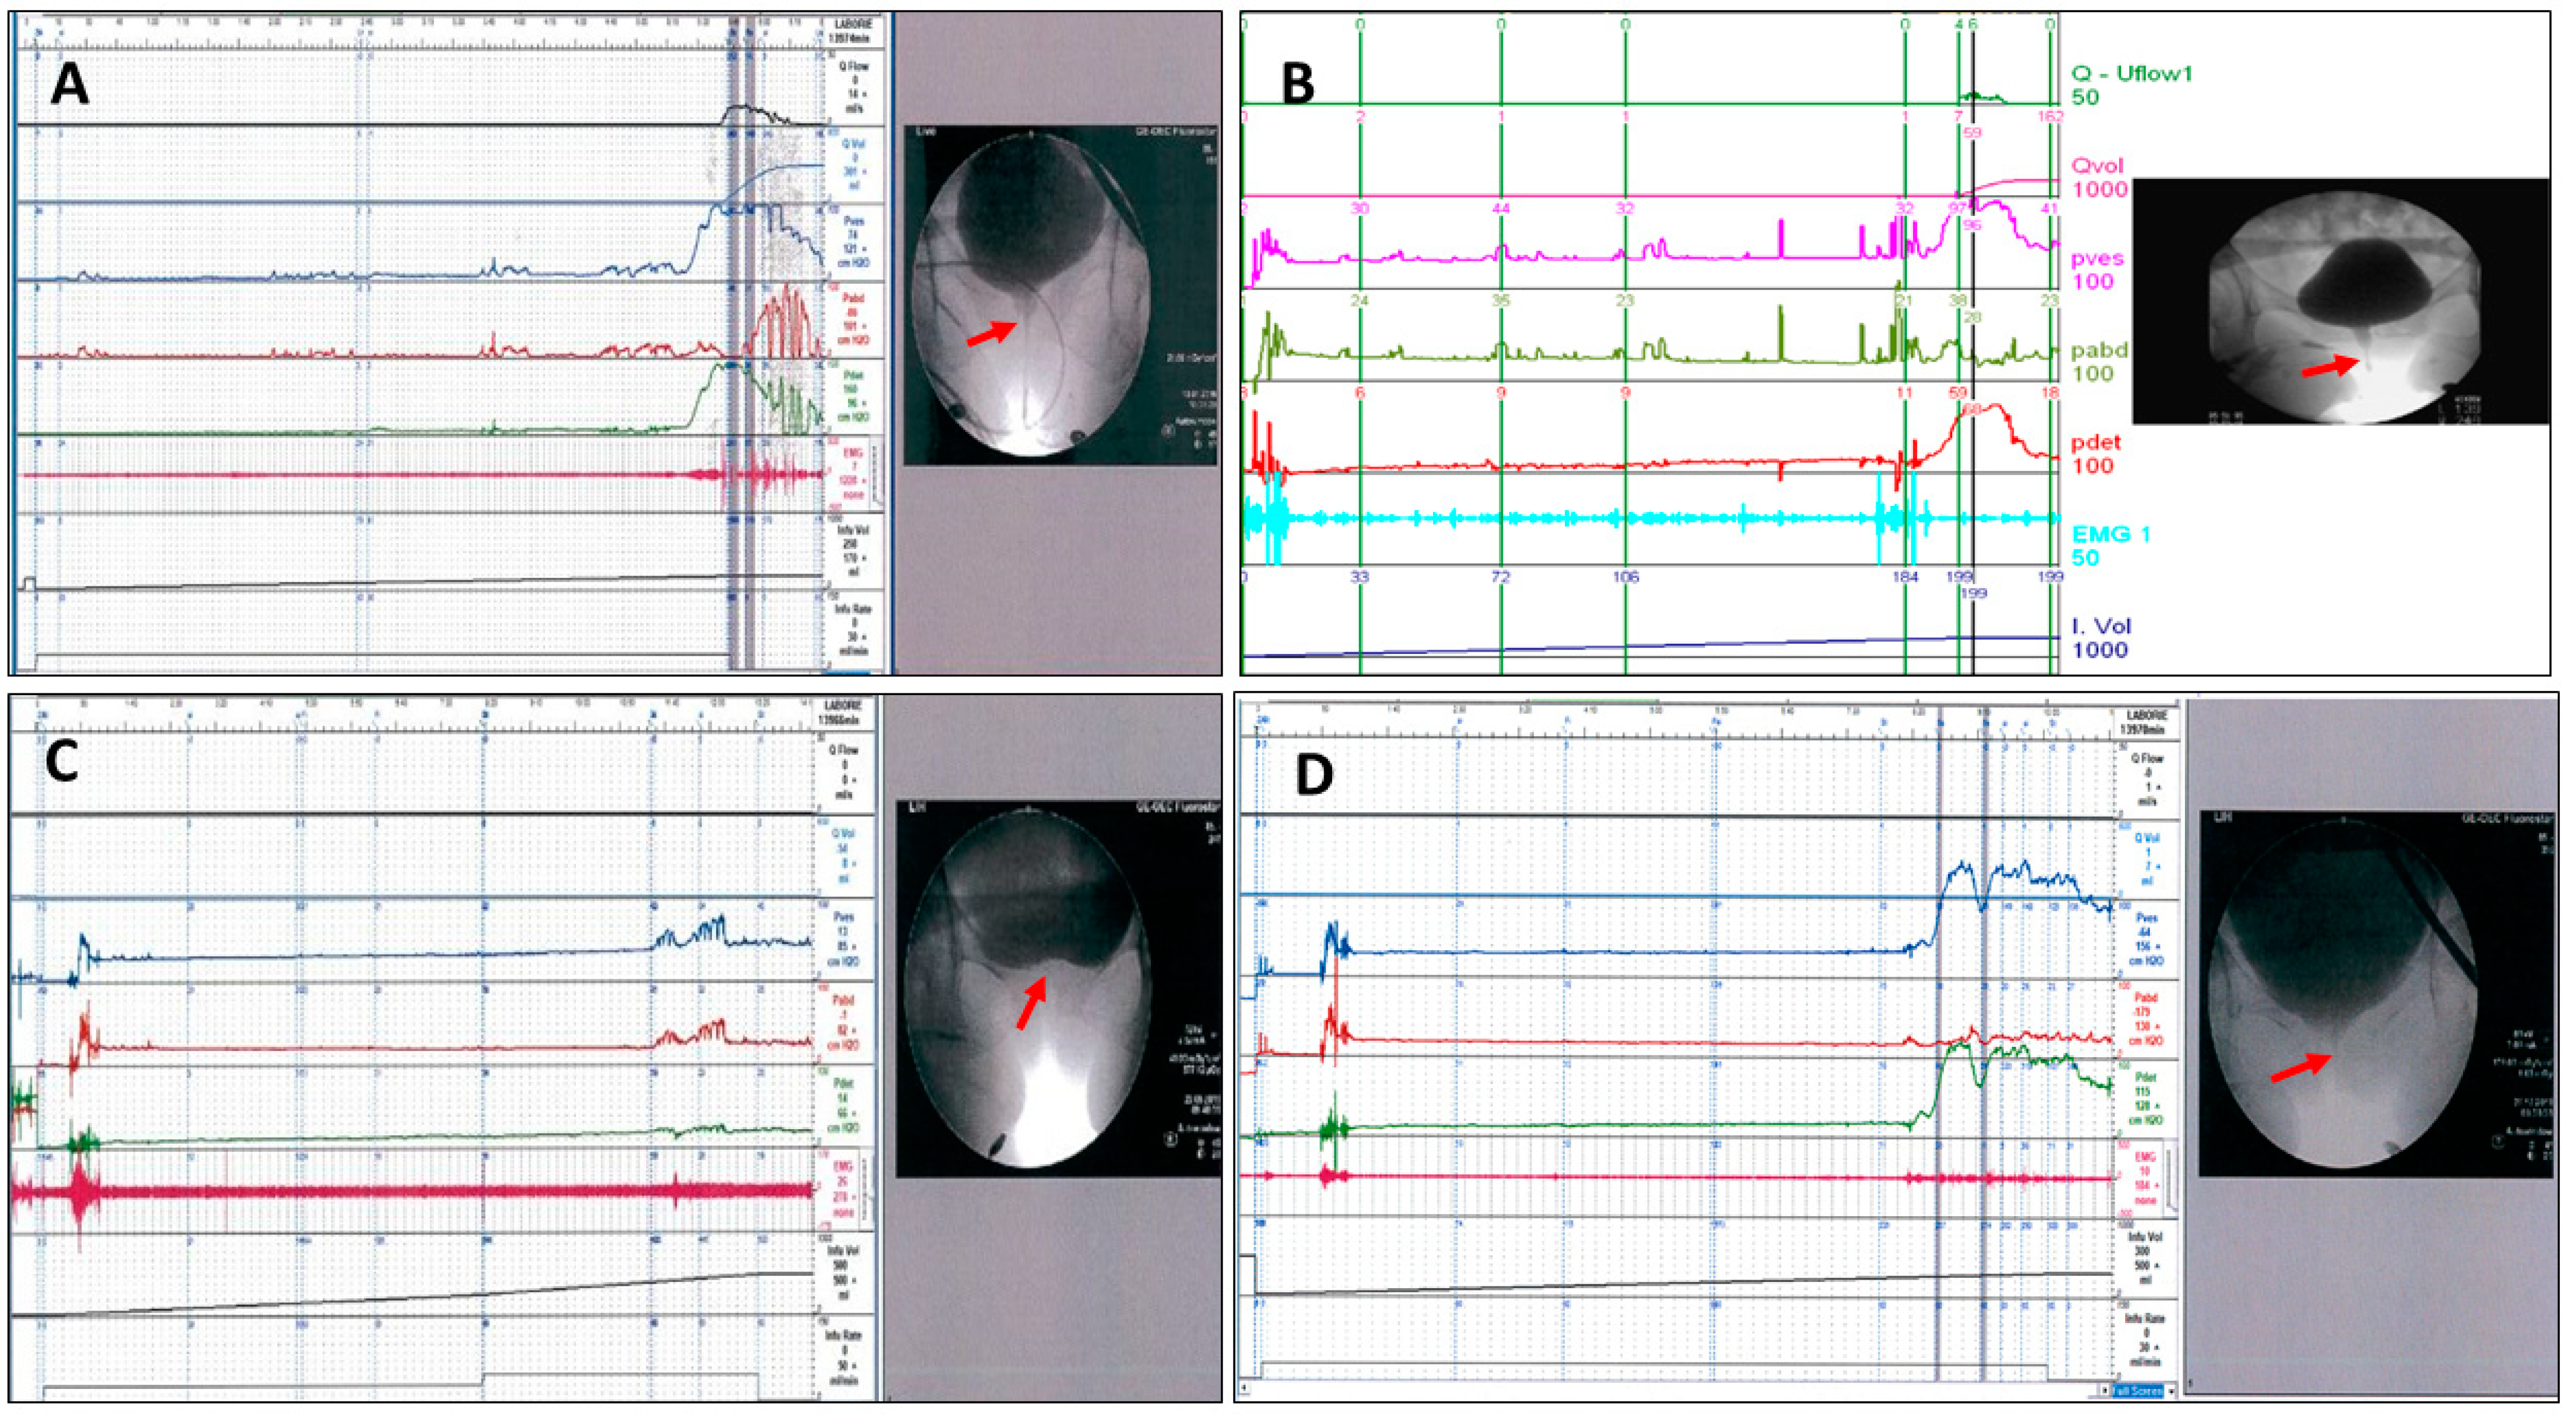

2. Results

5. Methods